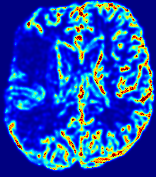

LesionRefer to captionRefer to captionRefer to captionRefer to captionRefer to captionRefer to caption𝐕rgbsubscript𝐕𝑟𝑔𝑏{\bf{V}}_{rgb}Refer to captionRefer to captionRefer to captionRefer to captionRefer to captionRefer to caption𝐕2subscriptnorm𝐕2{\|\bf{V}}\|_{2}Refer to captionRefer to captionRefer to captionRefer to captionRefer to captionRefer to captionRefer to caption3.53.53.52.82.82.82.12.12.11.41.41.40.70.70.70.00.00.0(mm/s)𝑚𝑚𝑠(mm/s)D𝐷DRefer to captionRefer to captionRefer to captionRefer to captionRefer to captionRefer to captionRefer to caption0.0200.0200.0200.0160.0160.0160.0120.0120.0120.0080.0080.0080.0040.0040.0040.0000.0000.000(mm2/s)𝑚superscript𝑚2𝑠(mm^{2}/s)Slice #1Slice #2Slice #3Slice #4Slice #5Slice #6

Figure 4: PIANO feature maps for another patient in the ISLES 2017 training set, where the lesion is located in the right hemisphere. Top row: segmented stroke lesion region (white) on different slices. The corresponding slices for the PIANO feature maps are shown in the following rows.

For a better insight into an estimated velocity field 𝐕𝐕{\bf{V}} and diffusion field 𝐃𝐃{\bf{D}}, we compute the following maps: (1) 𝐕rgbsubscript𝐕𝑟𝑔𝑏{\bf{V}}_{rgb}: Color-coded orientation map of 𝐕=(Vx,Vy,Vz)T𝐕superscriptsuperscript𝑉𝑥superscript𝑉𝑦superscript𝑉𝑧𝑇{\bf{V}}=(V^{x},V^{y},V^{z})^{T}, obtained by normalizing 𝐕𝐕{\bf{V}} to unit length and mapping its 3 components to red, green, blue respectively; (2) 𝐕2subscriptnorm𝐕2\|{\bf{V}}\|_{2}: 222 norm of 𝐕𝐕{\bf{V}}; (3) D𝐷D: scalar field in Eq. 5.

Fig. 3 and Fig. 4 show the PIANO feature maps estimated from two ISLES 2017 patients: all are highly consistent with the lesion in both cases. Details of the blood flow trajectories are revealed in 𝐕rgbsubscript𝐕𝑟𝑔𝑏{\bf{V}}_{rgb} by the ridged patterns and the sharp changes of colors in the unaffected (right) hemisphere, while the flat patterns appearing within the lesion provide little directional information about the velocity and indicate low velocity magnitudes. Velocity magnitudes are more directly visualized via 𝐕2subscriptnorm𝐕2\|{\bf{V}}\|_{2}, from which one can easily locate the lesion where 𝐕2subscriptnorm𝐕2\|{\bf{V}}\|_{2} is low. D𝐷D also indicates lower diffusion values in the lesion, though with less contrast potentially due to the fact that it captures the accumulated effect of CA diffusion at the voxel-level.